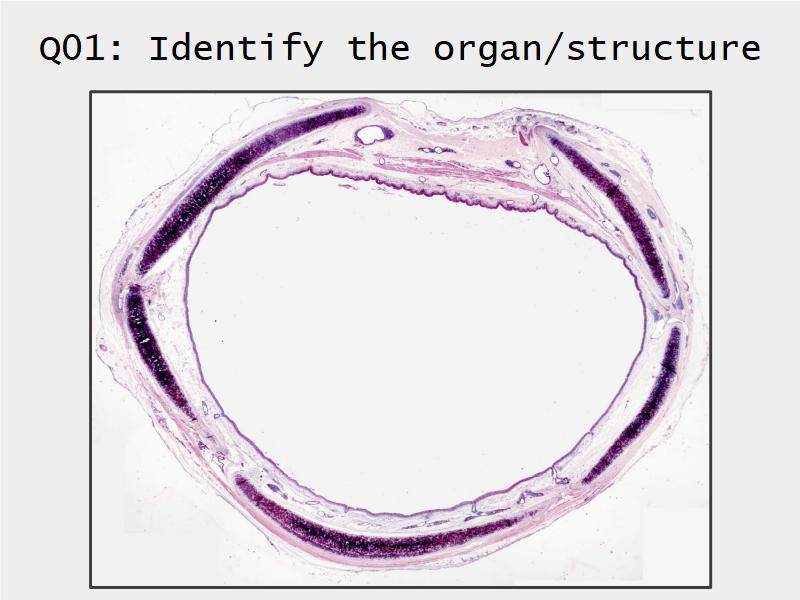

Respiratory Epithelium: Trachea

Today and Now I will do something for my future self.Trachea

- Slide 73: Trachea

Respiratory epithelium

- Pseudostratified

- Ciliated

- Columnar

- Epithelium with

- 4 Cells

- Ciliated columnar cells

- Non-ciliated columnar cells

- Goblet cells

- Basal cells